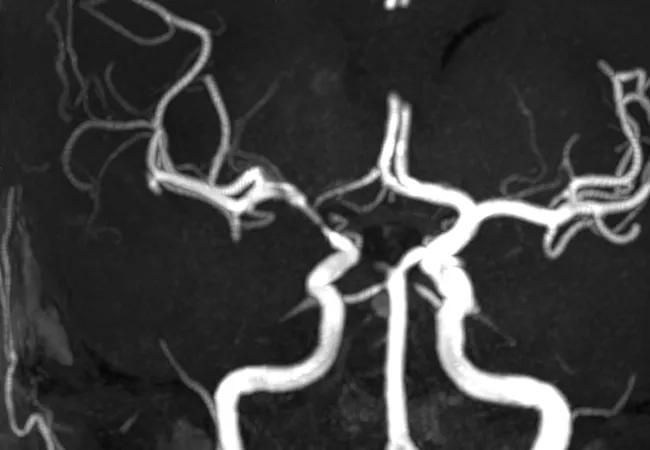

Imaging of vessels in CNS vasculitis

Primary angiitis of the central nervous system (PACNS) remains one of the most complex forms of vascular inflammatory disease. Multiple factors contribute to our relatively limited understanding of the disease including its rarity, the lack of an efficient noninvasive test, a paucity of pathological material to study and the absence of animal models simulating the disease.

In addition, more recent advances have discerned the importance of ruling out reversible cerebral vasoconstriction syndrome (RCVS), a major angiographic mimic of PACNS. The definition of RCVS as an entity in 2007 is considered a major breakthrough in understanding and eliminating the mimics of PACNS. Prior to 2007, RCVS was not well characterized, which may have added to the contamination of some of the PACNS cohort.